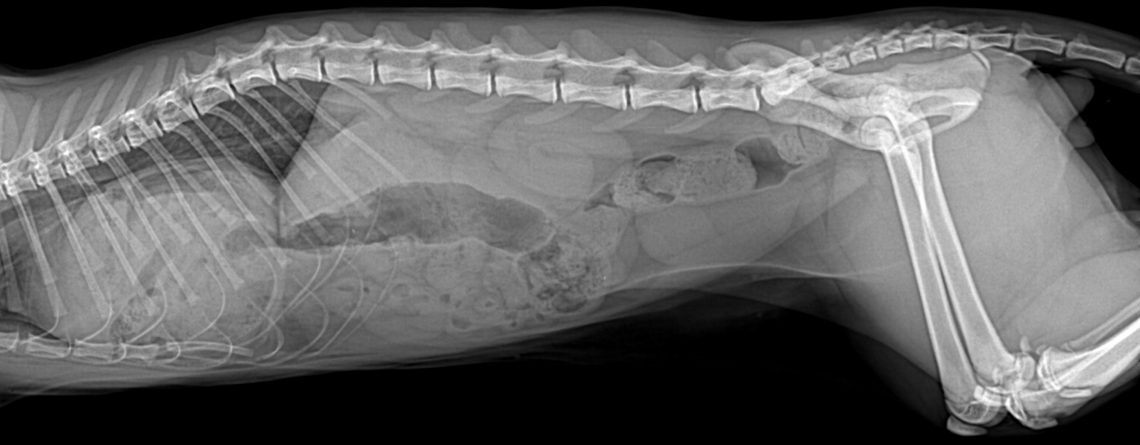

11 Aylık Kastre Edilmiş Scootish Fold Kedi

Anamnez 11 aylık, kastre edilmiş, Scottish Fold ırkı erkek kedide; iştahsızlık, kusma, kilo kaybı, öksürük şikayetleri vardır. Muayene...